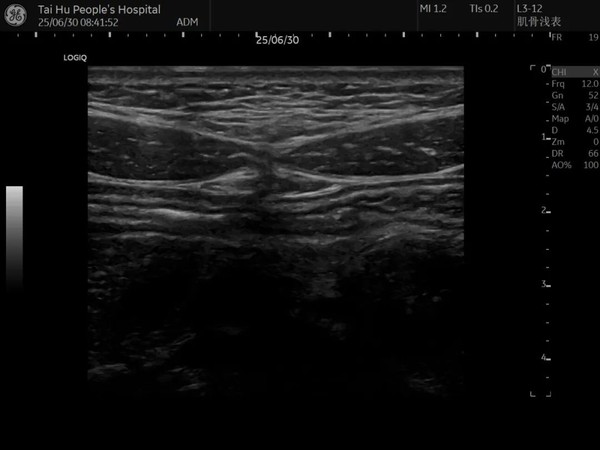

腹直肌分离常见于妊娠晚期、产后女性及肥胖人群,可能引发腰背疼痛、腹部膨隆、脏器移位等健康问题。传统触诊诊断主观性强且无法量化分离程度,而超声诊断凭借高分辨率、实时动态成像等优势,成为公认的"金标准"。太湖县人民医院超声医学科采用GE LOGIG E-11、EPIQ7C等超高端彩超仪等高端设备,通过高频探头对腹直肌进行多切面扫查,可精确测量腹直肌间距并评估肌肉收缩功能,整个检查过程仅需数分钟,无辐射且可重复,尤其适合产后42天及以上女性和长期腰背痛、腹部无力的人群。